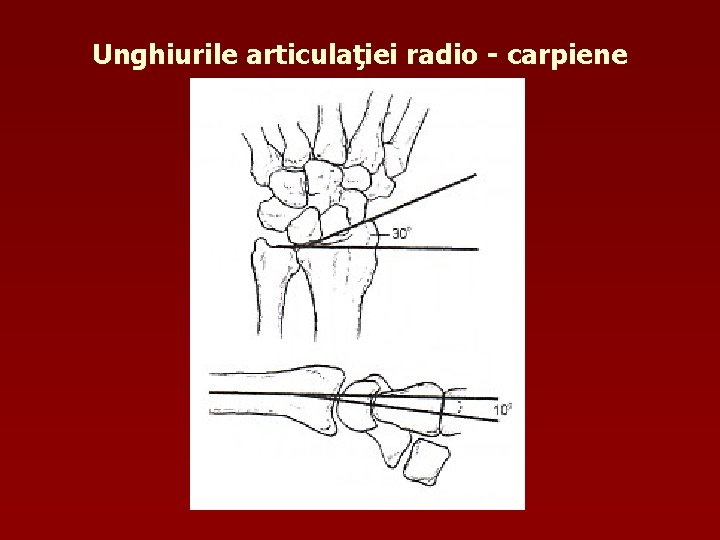

Unghiurile articulaţiei radio - carpiene